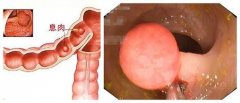

肠息肉

导语 肠息肉是肠道内的病变,它可小至芝麻、绿豆,也可大至核桃大

导语 肠息肉是肠道内的病变,它可小至芝麻、绿豆,也可大至核桃。数量可从

导语 肠息肉泛指肠道粘膜表面向肠腔突出的隆起性病变从病理上来看,其内容